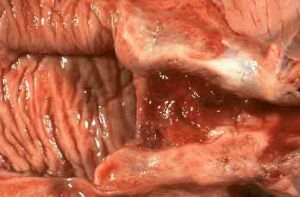

慢性子宮頸炎2、兩地湯 主要用於治療陰虛血熱而致的月經先期。今人用其方加減治療婦科手術後出血、經間期出血、功血等婦科常見疾病。